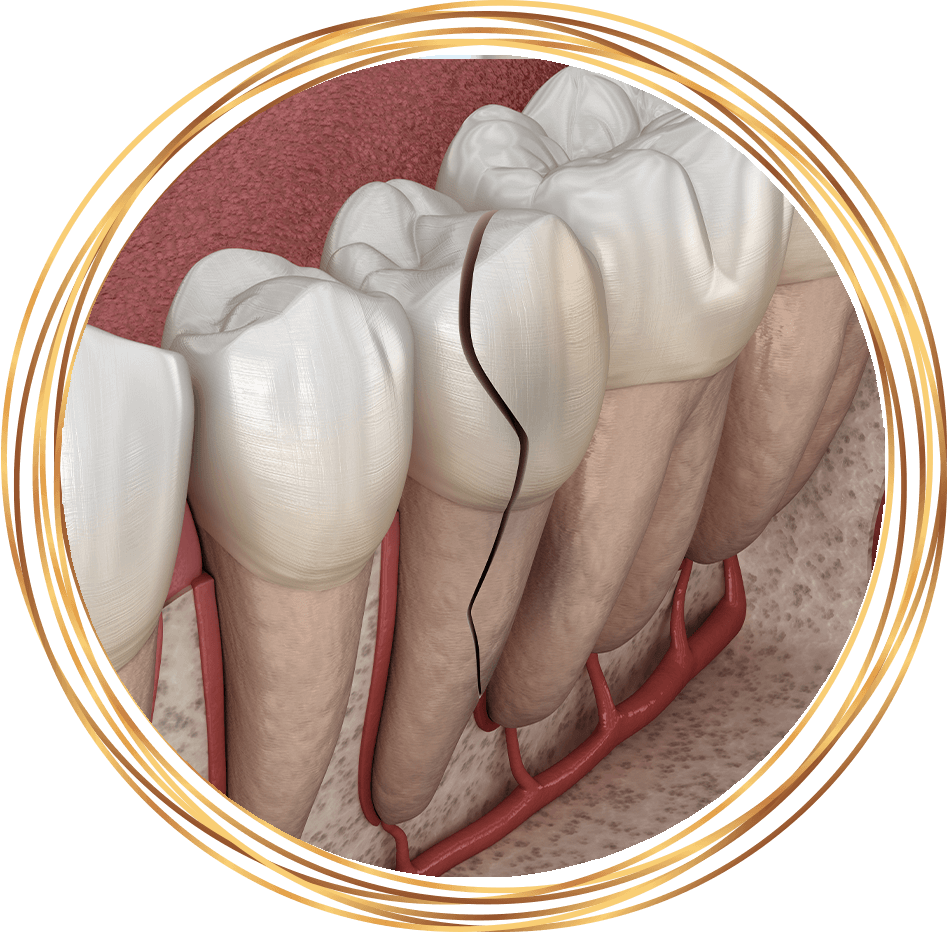

Tooth fractures can involve the crown, the root or both, with or without exposure of the pulp. Fractures that expose the pulp are often painful and require immediate treatment. Tooth fragments should be kept hydrated because we may be able to reattach them. Fractures of the root usually require digital X-rays for accurate diagnosis, unless the tooth is particularly loose and the fracture is close to the gingival margin. For root fractures, treatment may involve root canal therapy, splinting or extraction, depending on the exact nature and extent of the issue.

Luxation involving the pulp and/or supporting tissue accounts for 18–33% of injuries to permanent teeth. During an injury, a tooth can get pushed forward, backward or sideways, partially out of or into the socket. Types of luxation include intrusive, extrusive and lateral. Potential therapeutic options include passive repositioning (for intrusive luxation), manual repositioning (all luxation types), intentional replantation, orthodontic repositioning and splinting of the luxated tooth.